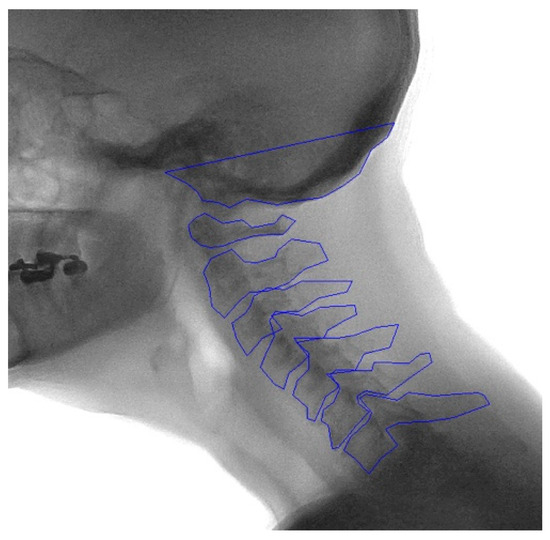

2.2. Manual Annotation

3.3. Mean Shape